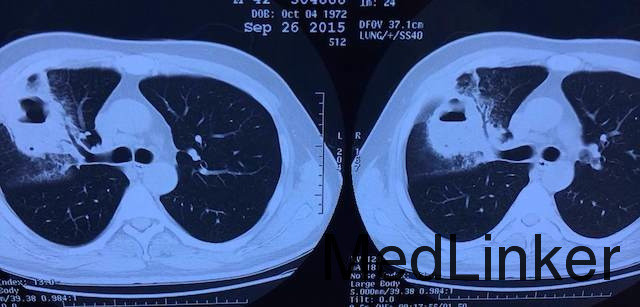

查体:体温38.℃,锁骨上淋巴结未触及肿大。 辅助检查:实验室检查:WBC 20*109/L,N% 87%。胸部CT如下:可见右肺空洞性占位,周围炎性渗出明显,可见支气管充气征。

随访:抗生素治疗8周后,复查胸部CT,脓腔和炎症消失,周围残存少量纤维灶。 讨论:一般肺脓肿多为吸入性肺脓肿,多合并厌氧菌,因此抗生素需覆盖厌氧菌;一般肺脓肿无需手术干预,需保证抗生素规范使用及脓液引流通畅;肺脓肿空洞需要癌性空洞(偏心性厚壁空洞)及结核性纤维性空洞继发感染(空洞壁较厚,一般无气液平,周围炎性渗出少,痰中可找到结合分枝杆菌)鉴别诊断。